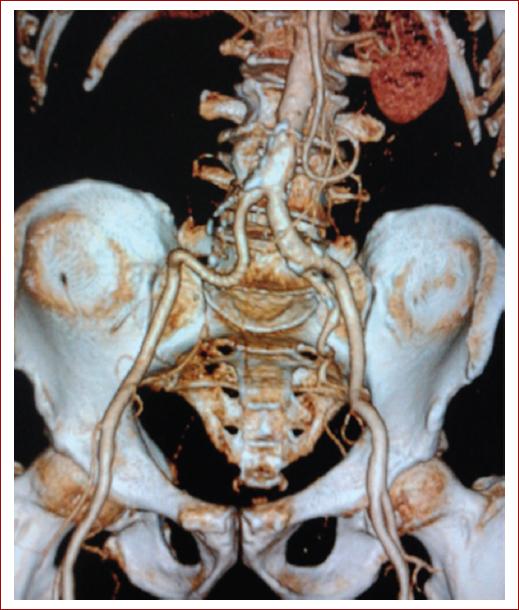

Por otro lado, para pacientes con síntomas, la tomografía computarizada (TC) abdominal y pélvica proporciona un diagnóstico más preciso. En concreto, la angiografía por TC es muy precisa para el diagnóstico de AAI y proporciona detalles extensos de la anatomía aortoilíaca (Fig. 2). También permite la caracterización de AAA coexistentes u otros aneurismas de arterias periféricas. Su inconveniente es la necesidad de uso de medio de contraste intravenoso y la exposición a radiación12,13.

Figura 2 A: angiografía por tomografía computarizada que muestra un aneurisma aislado de la arteria ilíaca común derecha. B: fotografía intraoperatoria que muestra un aneurisma de la arteria ilíaca común derecha (tomada de Goyal et al., 20143).

La vigilancia de por vida es necesaria para los pacientes tratados con técnicas endovasculares. La angiografía por TC y las mediciones del índice tobillo-brazo deben realizarse a los 30 días, seis meses y un año. Si no se observan problemas al año, el seguimiento puede limitarse a una TC anual o una ecografía abdominal para evaluar la permeabilidad de la endoprótesis, identificar cualquier endofuga y evaluar los cambios en el diámetro del saco del aneurisma. Si hay un aumento en el diámetro del saco del aneurisma o el paciente desarrolla síntomas, puede estar indicada una vigilancia más frecuente o una arteriografía (Fig. 6)26.

Figura 6 Angiografía por tomografía computarizada postoperatoria que muestra injerto permeable (tomada de Goyal et al., 20143).